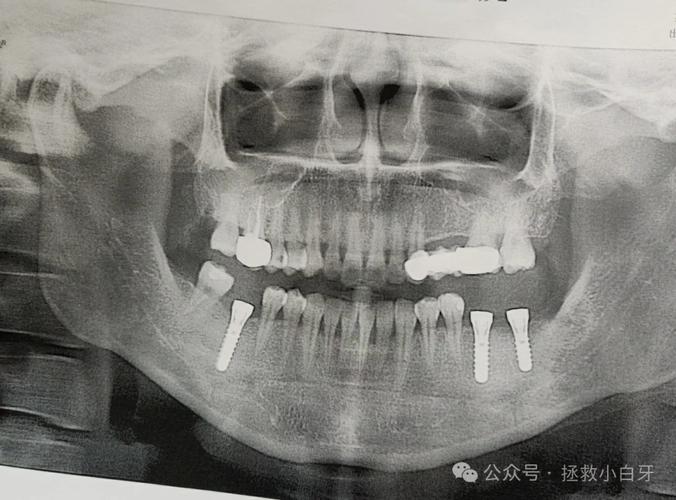

经过骨增量处理后,种植牙流程通常包括:术前检查(CBCT评估骨量、血常规等)、骨增量手术(如需要)、种植体植入(骨愈合期3-6个月)、基台安装、牙冠制作与戴牙,整个过程需3-6个月,具体时间取决于骨愈合速度和个体差异。